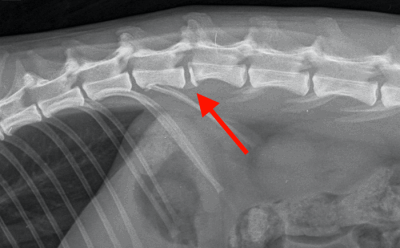

Osiris presented to Hamilton Specialist Referrals (HSR) as an emergency following a fall from height. Sadly, he was unable to use his back legs. His first opinion veterinary practice promptly identified that Osiris was paraplegic and acquired some radiographs of his back. These revealed a high suspicion of a spinal fracture at the location identified by the red arrows on the below images.

Osiris was assessed by our anaesthesia team and nurses who stabilised him so that he could be anaesthetised. Under a general anaesthetic, a CT of the back confirmed the fracture in his spine (red arrow on images below). The vertebral canal (green star) is where the spinal cord runs. The floor of the vertebral canal (blue lines) should be level and as you can see in the images there is a step in the floor, resulting in pressure on the spinal cord. The image on the right also shows a deviation in the spine (the purple lines should be straight), also adding pressure to the spinal cord. This pressure means that the neurotransmission pathway between the brain and legs is disrupted, which ultimately meant that Osiris couldn’t use his hindlimbs.